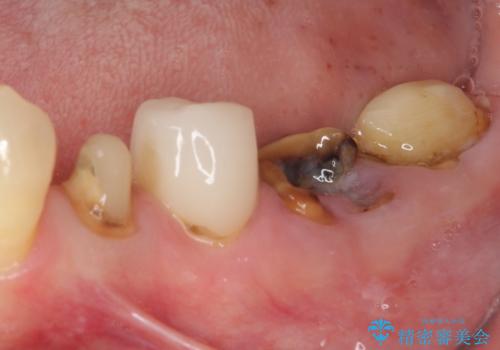

- 虫歯や歯の欠損を放置していることを気にして来院された患者様です。

下顎には抜歯が必要な歯があったため、抜歯後に治癒を待ち、上顎とともにオールセラミックブリッジにて補綴治療を行うこととしました。